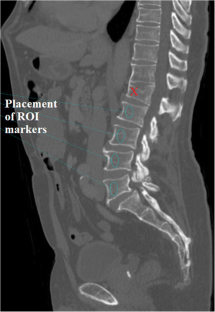

We included 109 Chinese patients who concomitantly underwent abdominal CT and dual X-ray absorptiometry (DXA) within 6 months between July 2014 and July 2017 at a university hospital in Hong Kong. Images were retrospectively reviewed on sagittal reformats, and region-of-interest (ROI) markers were placed on the anterior portion of each of the L1–L5 vertebra to measure the HU. The mean values of CT HU were then compared with the bone mineral density (BMD) and T-score obtained by DXA. Receiver operator characteristic (ROC) curves were generated to determine diagnostic cutoff thresholds and their sensitivity and specificity values.